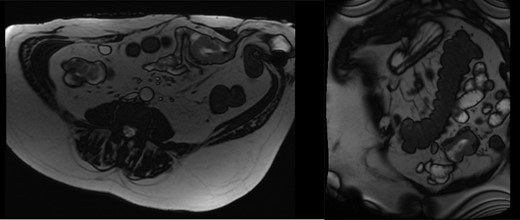

In 2017, repeat imaging showed resolution of all liver metastases, and the patient’s PSA was <0.1. While he had responded excellently to treatment, the patient had developed parastomal hernias around both the colostomy and ileal conduit. Between 2015 and 2017, the patient presented to hospital twice with features suggestive of small bowel obstruction. At the time, this was believed to be related to the hernias and therefore, the patient was planned for surgical repair of these hernias. During pre-operative workup, investigations revealed the patient to be anaemic with a haemoglobin of 80 and a ferritin of 11. Gastroscopy and colonoscopy revealed no abnormality; however, a pill cam demonstrated a single large lesion in the jejunum (Fig. 1). An MRI enterography was arranged to further characterize the lesion (Fig. 2). Given the excellent response to treatment, resolution of all liver metastasis and undetectable PSA levels a prostate cancer metastasis was not suspected. As the nature of this lesion was uncertain, a decision was made to perform a diagnostic laparotomy at time of hernia repair with small bowel resection if indicated.